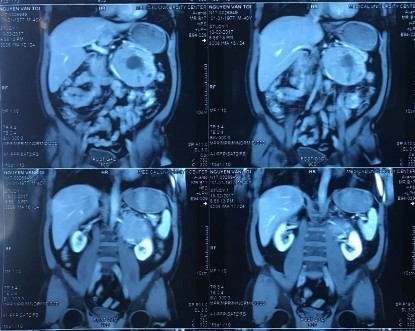

Hình 3.3: Phim CT scan bướu TTT bên trái chèn ép rốn thận trái

[Nguyễn Văn T., 40 tuổi, SNV: 2170024159]

Ghi chú: TH tổn thương TM thận trái trong phẫu thuật